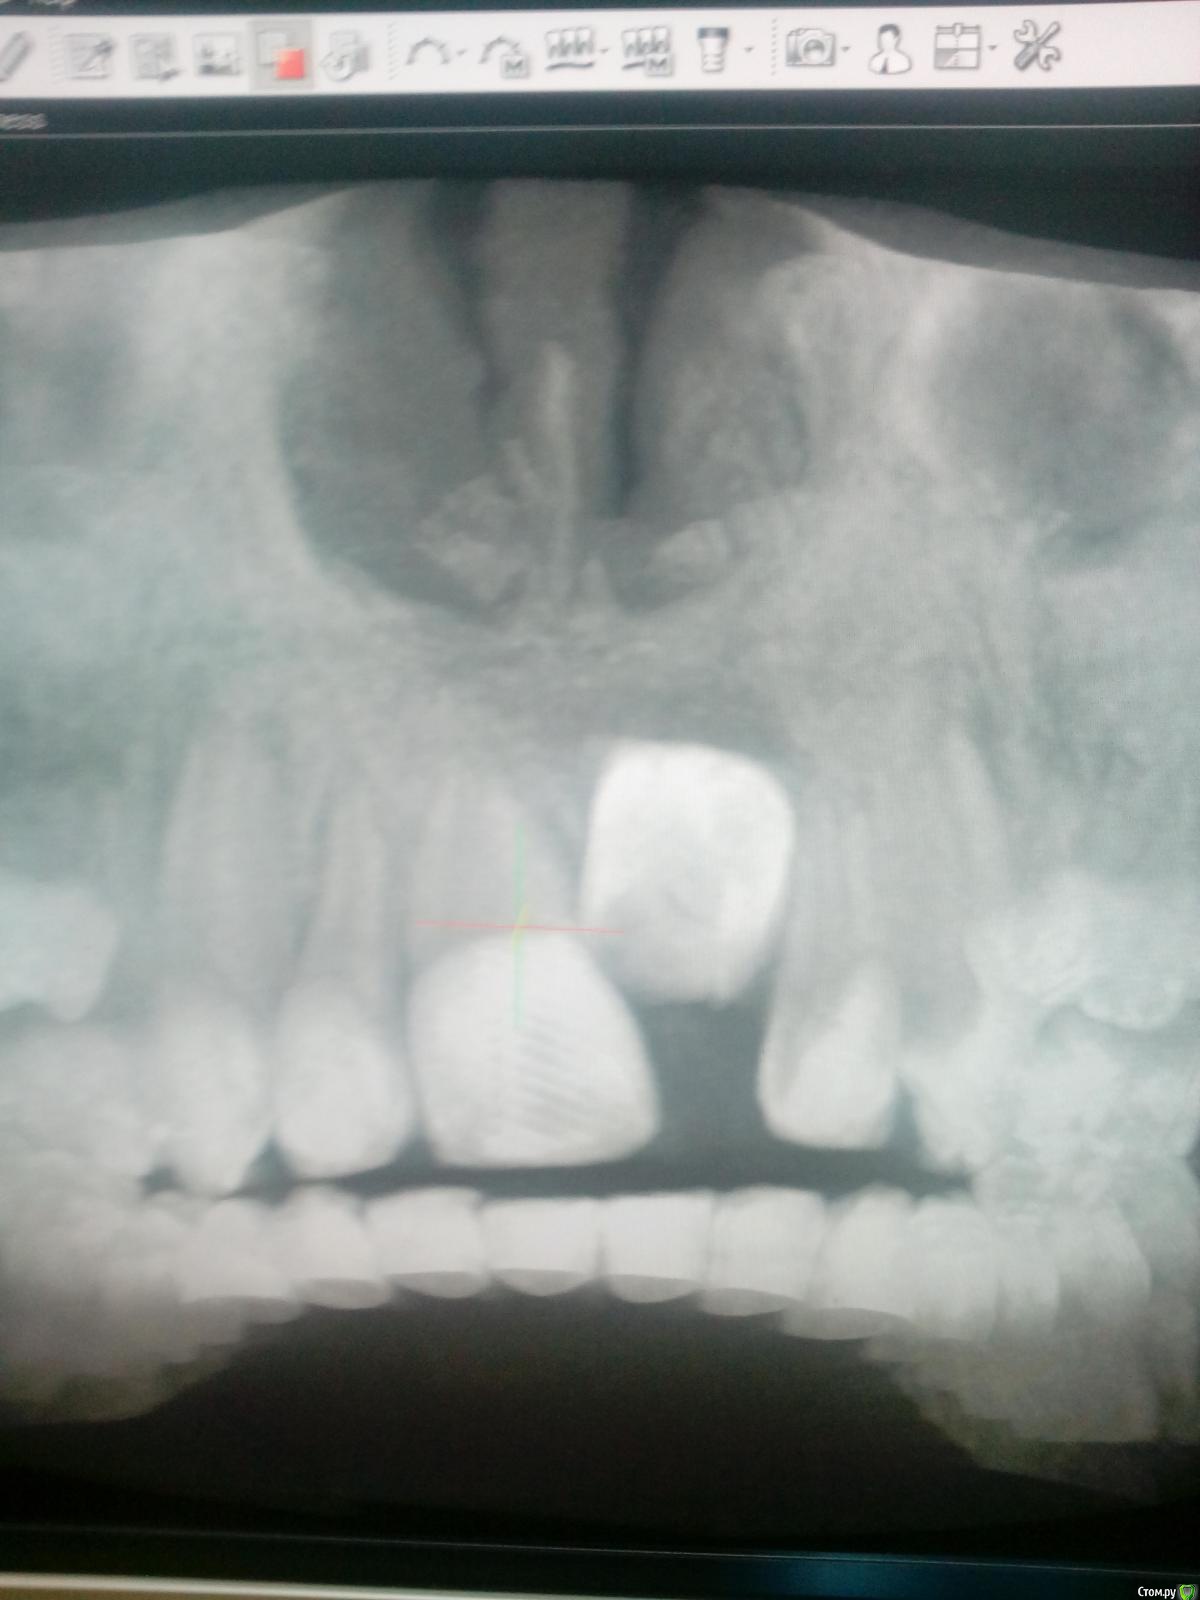

Opdihatop Опубликовано 9 января, 2017 Поделиться Опубликовано 9 января, 2017 Здравствуйте, коллеги! Хотел бы узнать ваше мнение по пациентке. Девочке 7 лет. План лечения в общем мне ясен и понятен. Меня интересует вопрос, когда лучше в данном случае убирать сверхкомплектный премоляр в области 21 зуба, потому что он начал двигать ц.л. вправо. Заранее спасибо! Ссылка на комментарий

Dok22 Опубликовано 11 января, 2017 Поделиться Опубликовано 11 января, 2017 Это не премоляр просто так виден 2-х мерный срез нужно КТ его грамотная интерпретация и хороший хирург.Сверхкомплектный удалять надо он блокирует 21 и 22. Ссылка на комментарий

Dok22 Опубликовано 12 января, 2017 Поделиться Опубликовано 12 января, 2017 С одной стороны вы правы риск повредить 21 22 есть,но если сверхкомплектный 21 сформируется полностью все будет сложнее сейчас при наличии грамотного КТ и хирурга зачаток сверхкомплектного 21 убрать проще.Убирал подобное в 6 и 9 лет в 9 сложнее. Попробую найти КТ выложить. Ссылка на комментарий

Dok22 Опубликовано 21 января, 2017 Поделиться Опубликовано 21 января, 2017 Это фотоаппарат врет, вмешательство от 4.01.2017. Родители получили инструкции+скайп ждем.Док не надо бояться начните с простого,кто если не мы? Делал так :1) Перед вмешательством седация.Анестезия.2) Вырезал лоскут с надкостницей, создав окно примерно 1кв.см.(чтоб не бороться с краями раны, я так и 8 убираю)3) Компактостеотомия ультразвуковым алмазом(кость мягкая режется легко ,им же режем сверхкомплектный зуб бывает вертится в ране можно фиксировать гладилкой)4) Сегментируем зуб,выбираем фрагменты(обязательно тщательно убрать ростковую капсулу сверкомлектного,обильно промыть водой.Аккуратно проконтролировать отсутствие ростковой зоны!!!)5) Рана не ушивается, только тампонада как при обычном удалении.6) Инструкции родителям(отеки,субфебрильная температура,болезненность это нормально не более суток,при болях детское) Вам нужен ассистент,тонкий кровоотсос,обычный слюноотсос,тонкий элеватор(3-4милиметра) и самое важное ТЕРПЕНИЕ.Спрашивайте. 1 Ссылка на комментарий